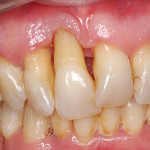

La terapia implantare nel paziente parodontopatico

Riassunto

Nei pazienti affetti da parodontite avanzata ci si trova spesso, alla fine della terapia parodontale, nella necessità di riabilitare dei settori edentuli più o...